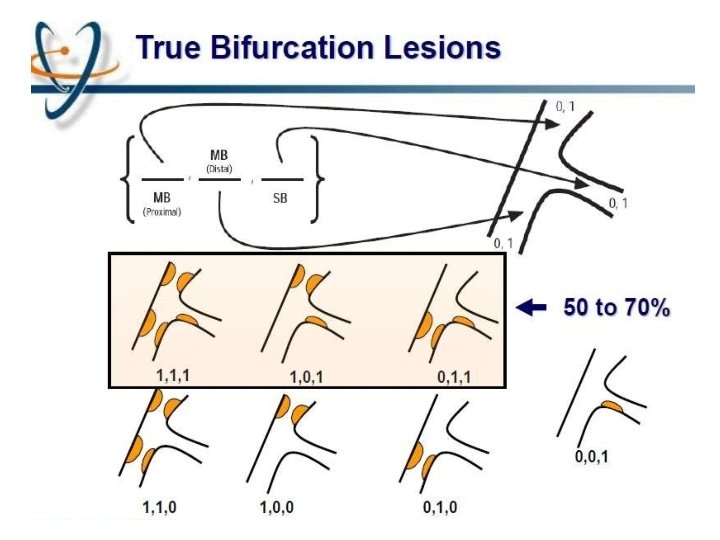

MEDINA classification

Limitations Does not take intoaccount 1. 2. 3. 4. 5. 6. Length of disease in the ostium of the SB Length of the LMCA before the bifurcation Trifurcation Vessel angulation No differentiation is madebetween a normal segment (lesion free segment) and a < 5 0 % lesion presenceof calcifications is not identified